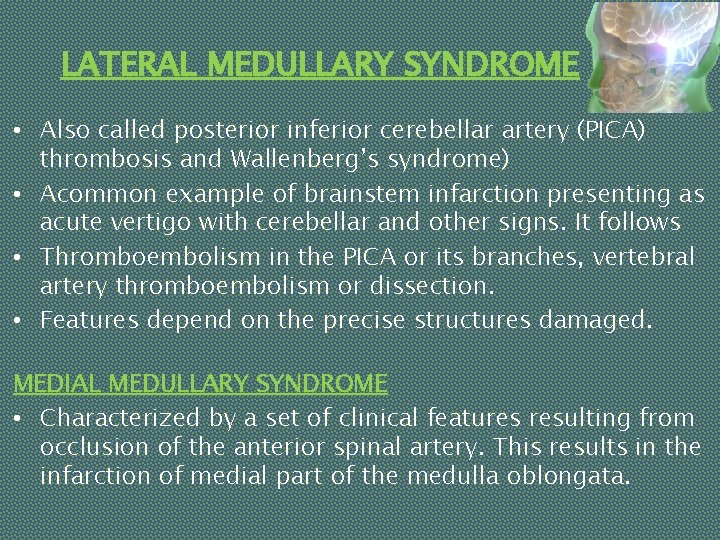

LATERAL MEDULLARY SYNDROME • Also called posterior inferior cerebellar artery (PICA) thrombosis and Wallenberg’s syndrome) • Acommon example of brainstem infarction presenting as acute vertigo with cerebellar and other signs. It follows • Thromboembolism in the PICA or its branches, vertebral artery thromboembolism or dissection. • Features depend on the precise structures damaged. MEDIAL MEDULLARY SYNDROME • Characterized by a set of clinical features resulting from occlusion of the anterior spinal artery. This results in the infarction of medial part of the medulla oblongata.